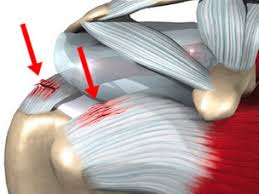

۳. آسیب های ناگهانی

افتادن روی دست یا ضربه مستقیم به شانه می تواند باعث پارگی جزئی یا التهاب تاندون شود. این نوع آسیب معمولا با درد شدید و محدودیت حرکتی همراه است.

۳. درمان جراحی

در صورتی که درمان های غیر جراحی موثر نباشند یا تاندون دچار پارگی کامل شده باشد، جراحی مورد نیاز است.

در این روش، پارگی تاندون ترمیم می شود و ساختار طبیعی مفصل بازسازی می گردد.